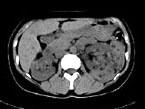

问题 女,36岁,左侧腰痛2 年余,CT检查如图所示,下列说法错误的是 ( )

选项 A、考虑为肾癌 B、考虑为双肾错构瘤 C、左肾病灶中可见脂肪密度灶,该区增强时也无强化 D、右肾中极可见一小的类圆形混杂密度病灶 E、左肾下极可见一混杂密度病灶,其边界尚清

答案 A